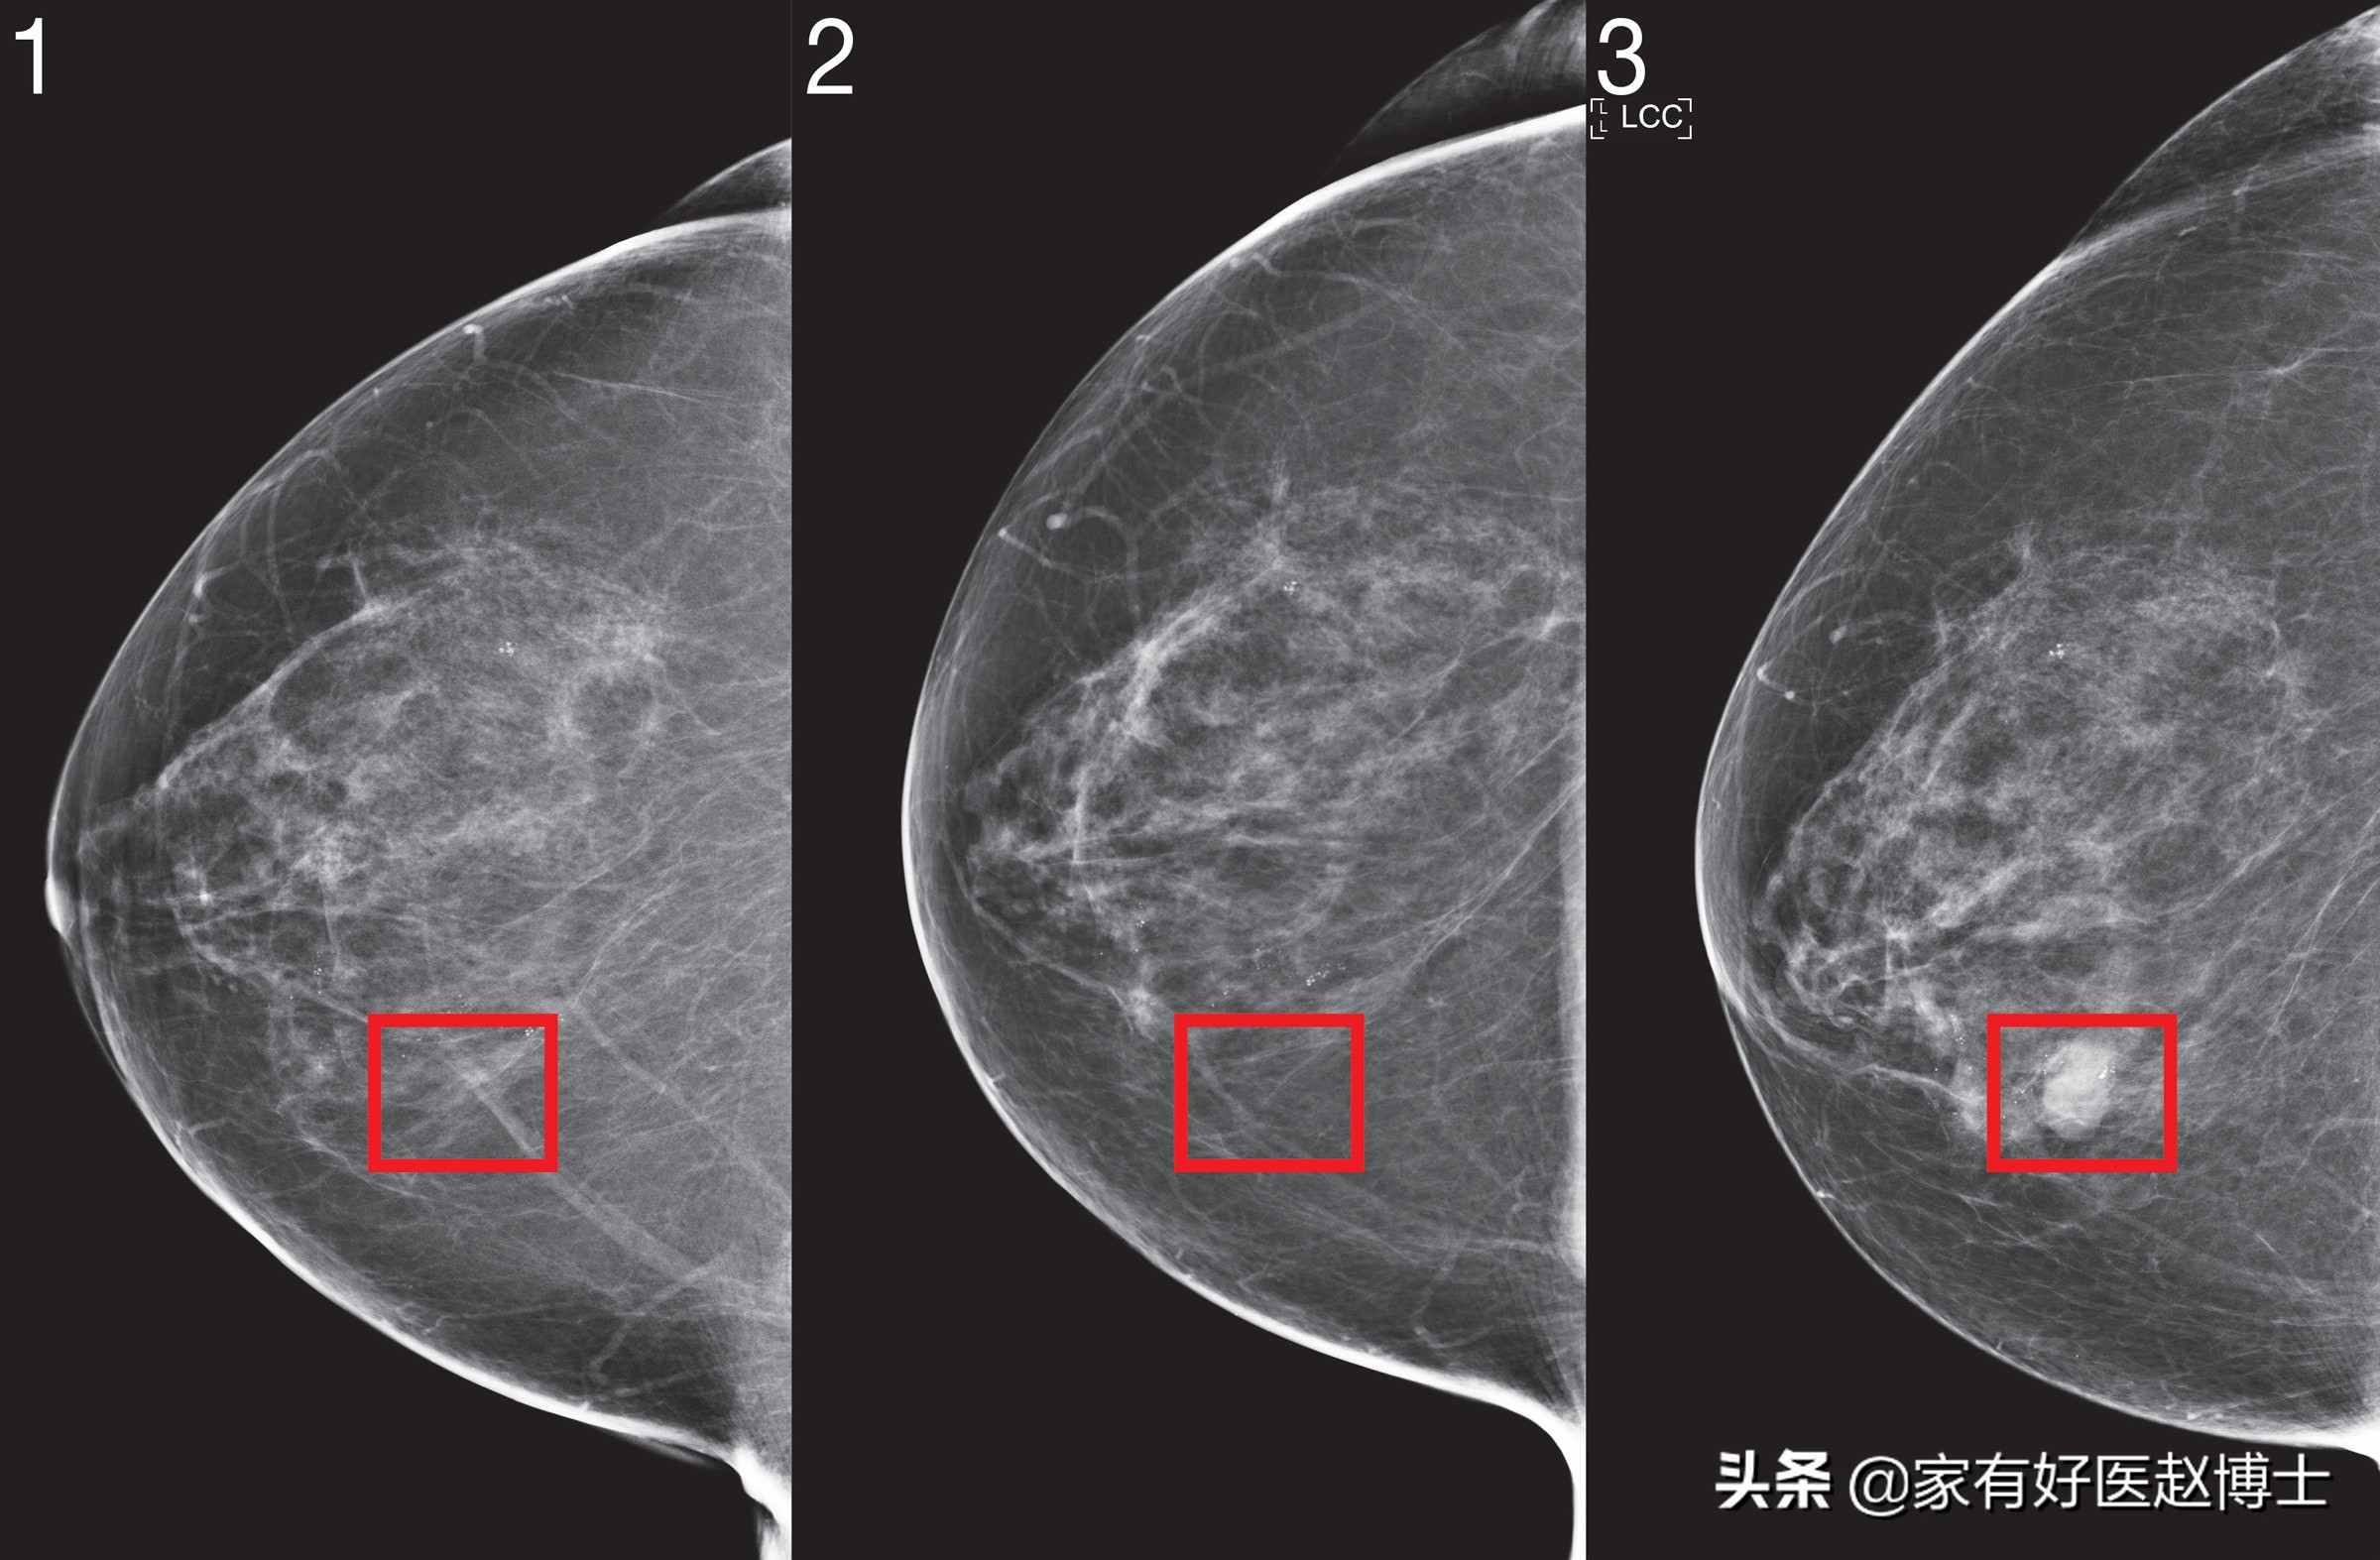

筛查乳腺癌最常用的有两种技术,乳腺X线摄影和乳腺超声。最普通的乳腺癌筛查,一般可以优先使用乳腺X线摄影。

但是,在某些特殊情况下,比如乳腺癌的高风险人群或致密型乳腺人群,则可能需要同时做这两种检查以相互补充。

必要的时候,甚至在做完了这两项检查以后还需要增加乳腺核磁共振的扫描。

这里大家只需要记住一点即可,这就是乳腺癌的筛查有时候不是只做某一项检查就够了,有可能需要同时做两种甚至三种检查。